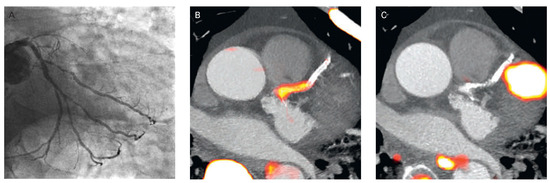

Figure 14. Focal 18F-fluoride and 18F-fluorodeoxyglucose uptake in a patient with acute ST-segment elevation myocardial infarction. (A) Proximal occlusion (red arrow) of the left anterior descending artery on invasive coronary angiography and (B) intense focal 18F-fluoride (18F-NaF, tissue-to-background ratios, culprit 2.27 versus reference segment 1.09 uptake (yellow-red) at the site of the culprit plaque (red arrow) on the combined positron PET/CT). (C) Corresponding 18F-fluorodeoxyglucose PET-CT image signifying no uptake at the site of the culprit plaque (18F-FDG, tissue-to-background ratios, 1.63 versus reference segment 1.91. Of note, the significant myocardial uptake overlapping with the coronary artery (yellow arrow) and uptake within the oesophagus (blue arrow). Reprinted from: Joshi NV, Vesey AT, Williams MC, Shah AS, Calvert PA, Craighead FH, et al. 18F-fluoride positron emission tomography for identification of ruptured and high-risk coronary atherosclerotic plaques: a prospective clinical trial. Lancet. 2014;383:705–13, with kind permission.